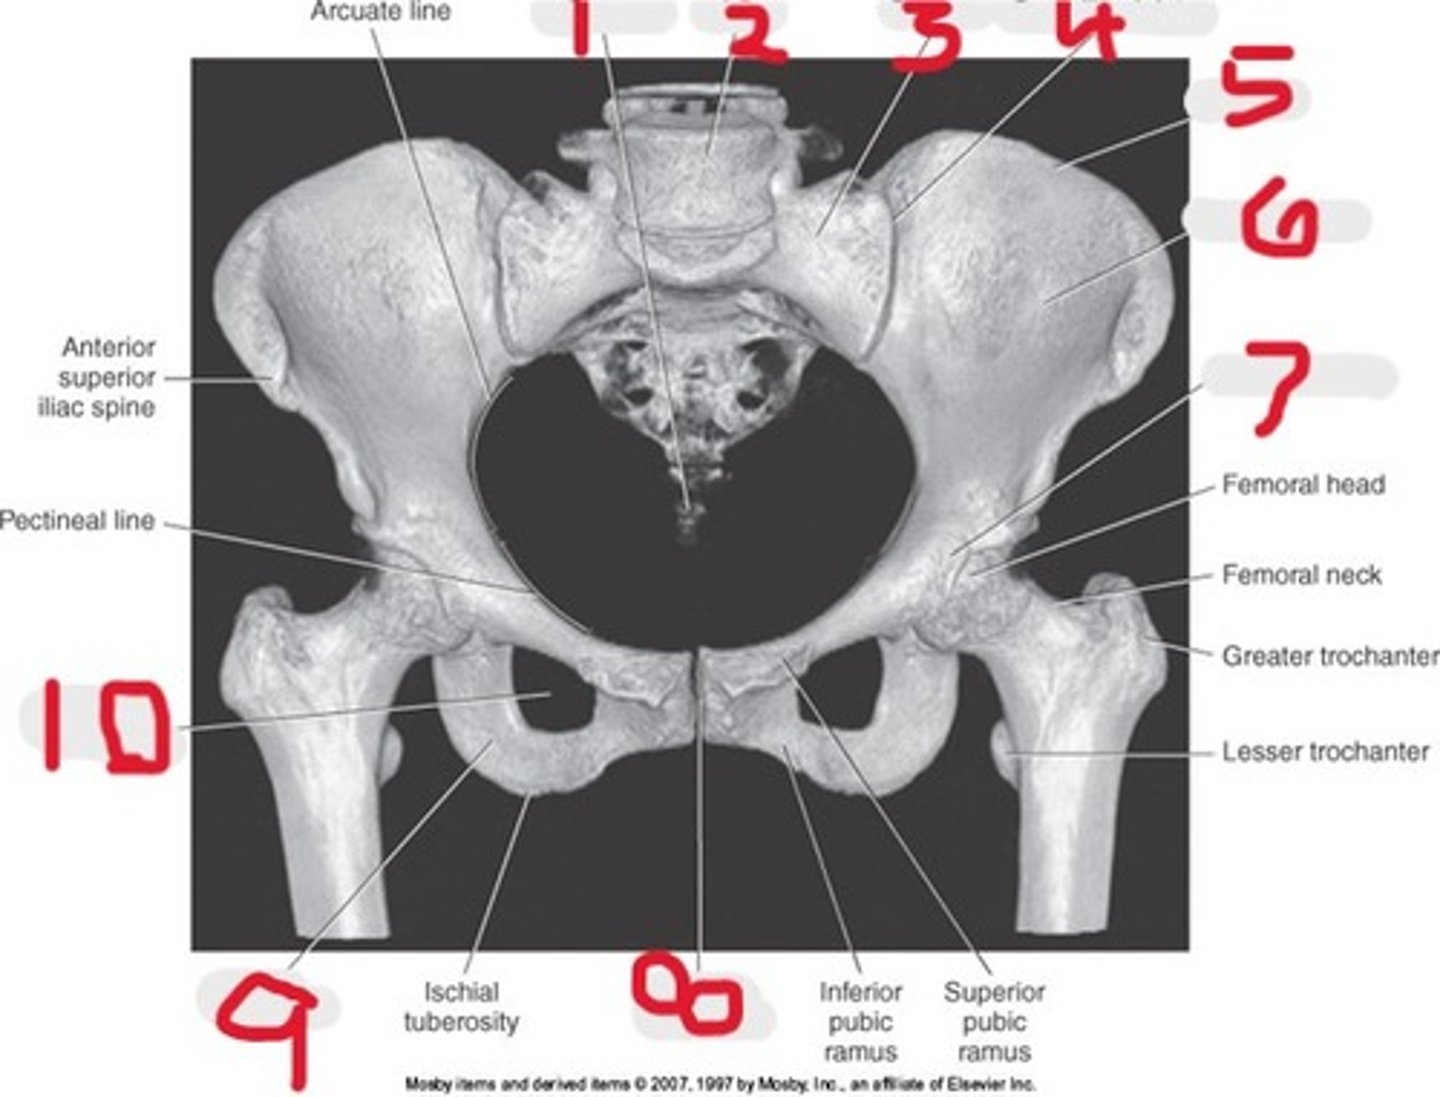

1) Iliac crest

2) Ilium

3) Acetabulum

4) Pubic symphysis

5) Ischium

6) Coccyx

7) Ala of ilium

8) Lateral mass (ala)

9) Sacrum

10) SI joints

Name all numbered structures